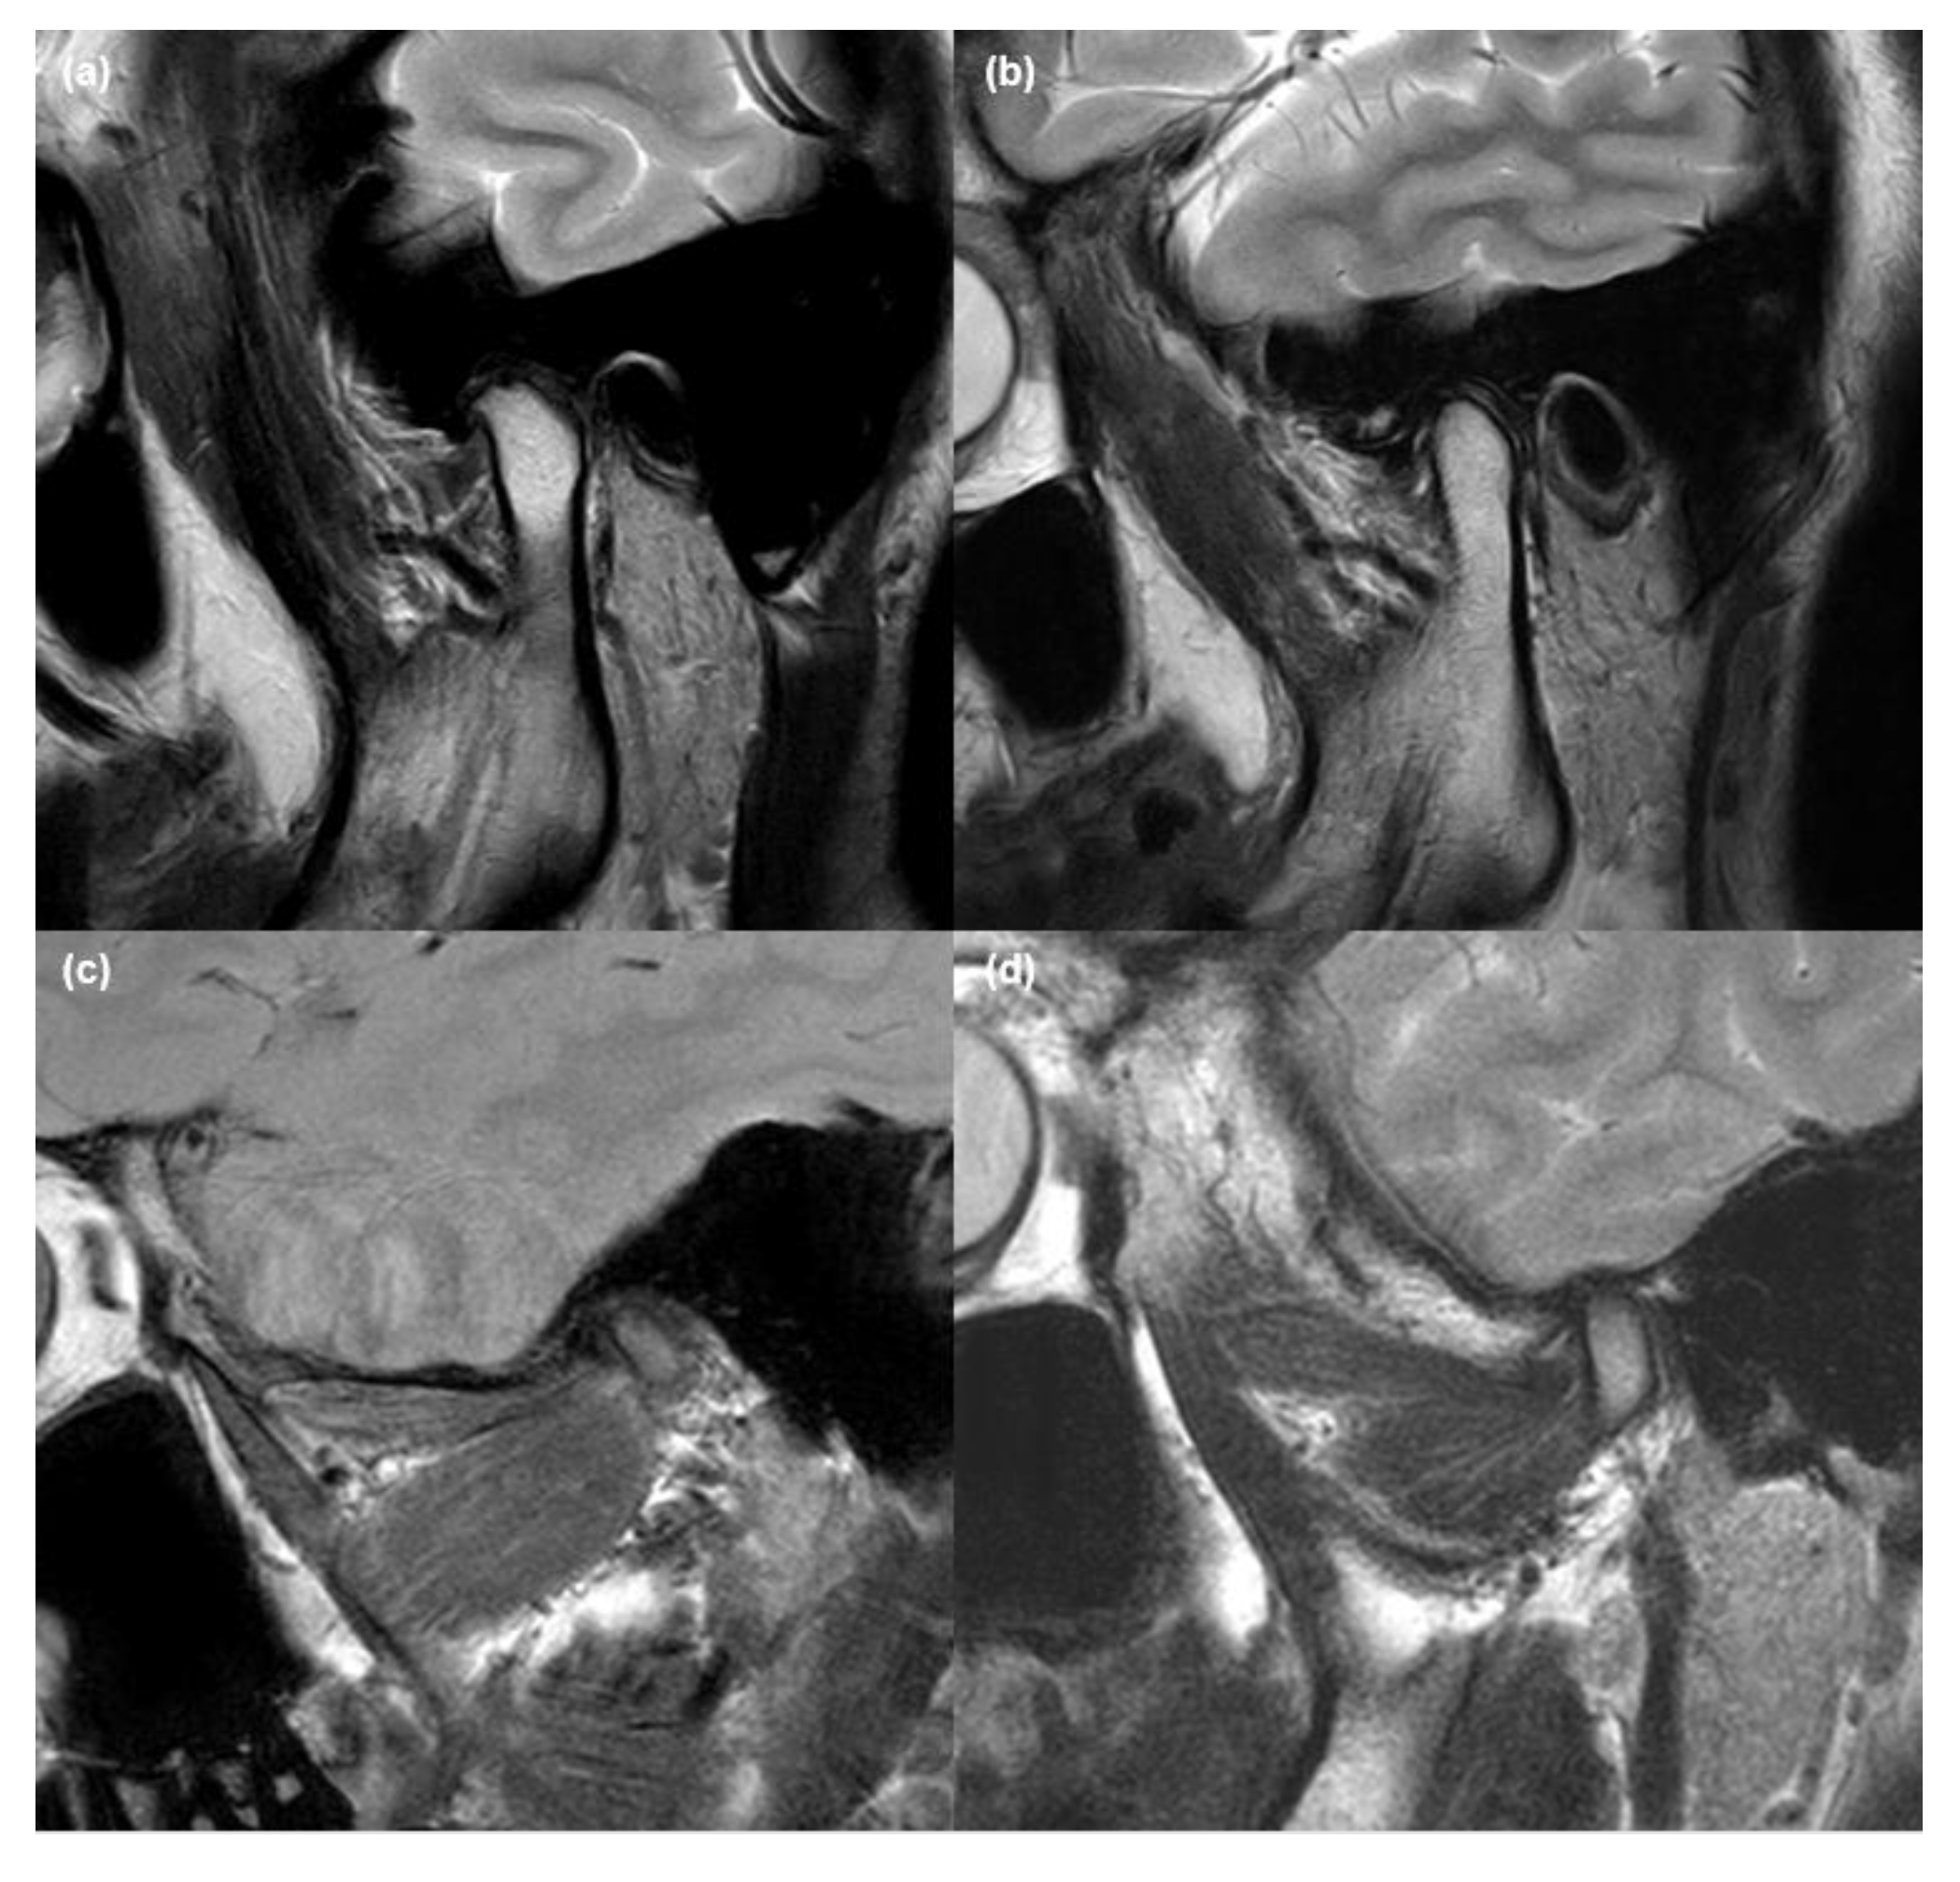

2.2. MRI Acquisition and Analysis